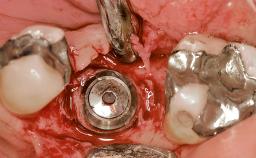

This 41-year-old female patient was referred to the clinic for the replacement of the right central incisor, since the tooth had developed a root fracture in the long axis that made extraction necessary. The healthy, non-smoking patient was first seen with the tooth still in place. A detailed Esthetic Risk Assessment was performed.The patient was worried about her dental esthetics and had high expectations for a successful treatment outcome from an esthetic point of view. The patient had a medium lip line that displayed parts of the gingiva in the anterior maxilla upon smile.

| Bone Augmentation | Horizontal|Simultaneous |

| Augmentation Materials | Autogenous chips|Xenogenous|Membrane |

| Bone Volume | Deficient horizontally, allowing simultaneous augumentation |